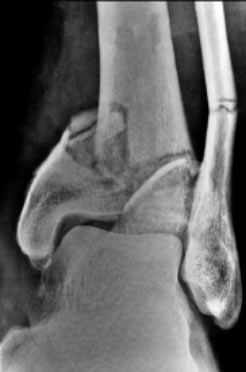

Ankle